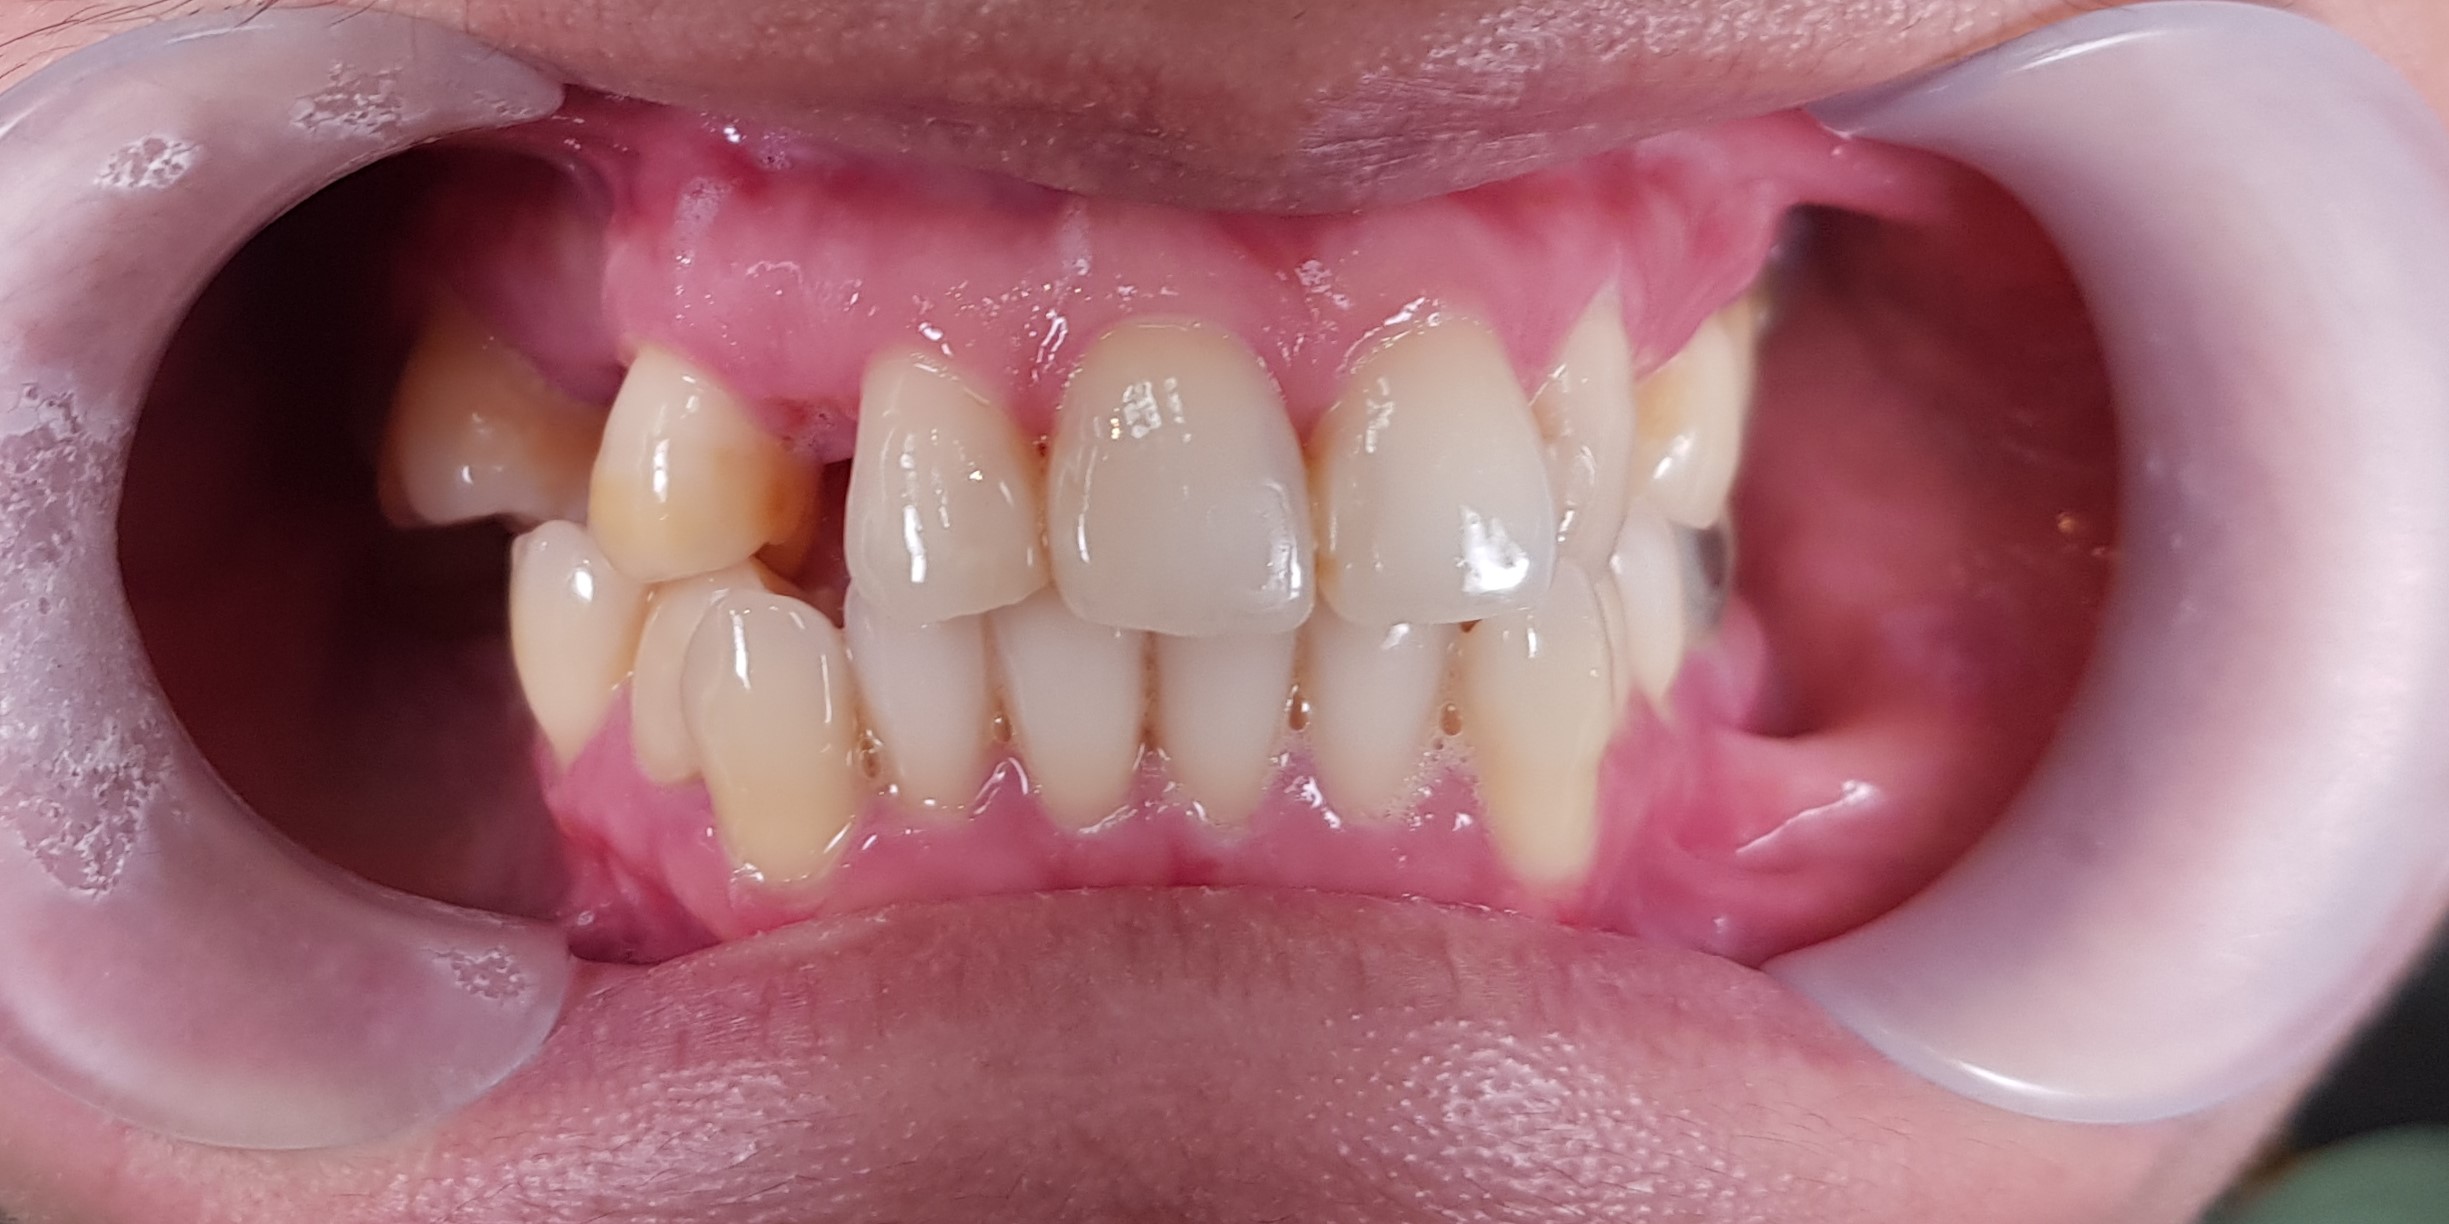

Abstract: Removable partial denture is a definitive prosthesis that has been used in dentistry for decades for the rehabilitation of partially edentulous patients. The visibility of the retentive arm in the metal denture sometimes causes esthetic problems for the patient. Therefore, aesthetic aspects should be considered to ensure patient satisfaction in dental treatment. This case report described oral rehabilitation using a combination of metal frame partial denture and thermo-plastic. A 40-year-old female patient with a history of old removable partial denture came to replace the old denture with a new one that was more aesthetic and showed no wire. The management of the patient included thorough anamnesis, extra and intra oral examinations, anatomic impression, determination of definitive treatment, preparation of rest on the abutment tooth, physiological impression, manufacturing of metal frameworks in the upper and lower jaws, determination of definitive vertical dimension, try-in denture, insertion, and control of combination of a metal frame partial denture with thermoplastic in the upper and lower jaws. The patient was satisfied with her new denture.  In conclusion, the combination of a metal frame partial denture with thermoplastic can be an alternative treatment for patient who wants to replace his/her missing teeth with removable partial denture while still prioritizing aesthetic factors.